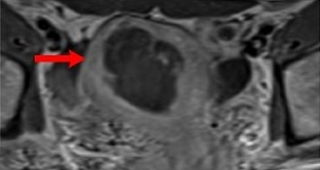

자궁근종 비수술 하이푸 치료 후 임신분만사례입니다. 아직 자녀가 없으신 분으로 복부에 만져지는 증상으로 자궁근종 하이푸 치료를 위해 내원하였습니다. 하이푸 시술전 MRI 사진상 자궁은 7.5cm 크기로 자궁전벽의 ...